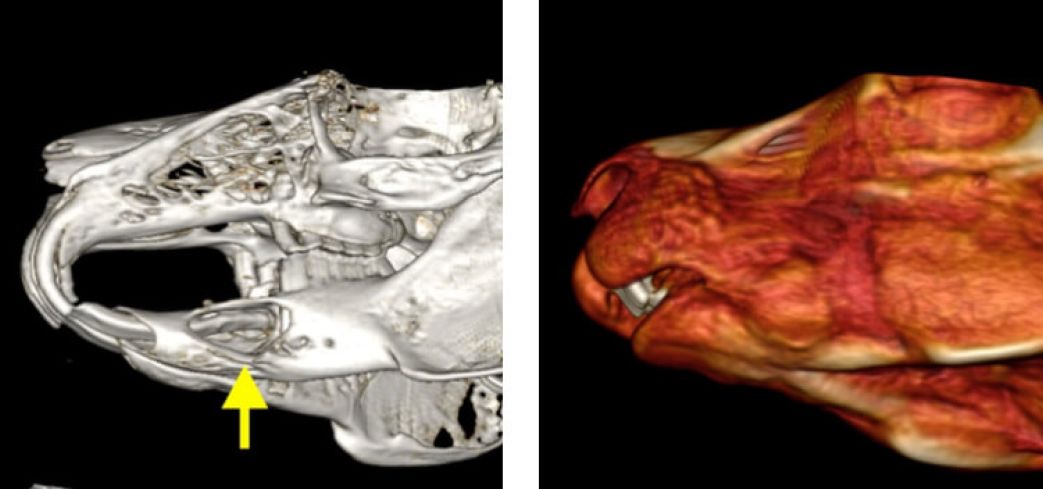

L’esame TAC rappresenta ormai il gold standard per la valutazione delle patologie del cavo orale di conigli e piccoli roditori (cavie, cincillà…). Per le caratteristiche particolari dei loro denti, infatti, conigli e piccoli roditori sono predisposti a problemi di malocclusione, allungamento dentale, ascessi e fratture. In tutte queste situazioni, la TAC garantisce la massima precisione diagnostica, più accurata di quanto si riesca ad ottenere dalle tradizionali radiografie. La possibilità di ricostruzione in 3D in corso di patologia dentale, inoltre, rappresenta un valido aiuto pre-operatorio per programmare un intervento dentale.